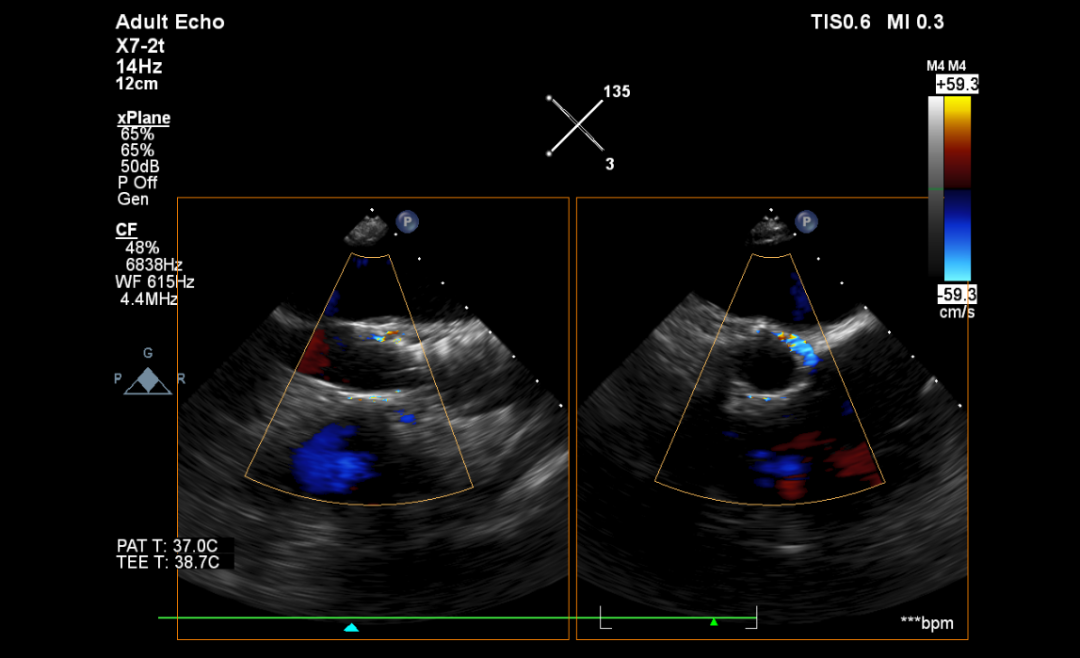

心超:主动脉退变伴重度狭窄,轻、中度反流,瓣上最大流速4.1m/s,平均压差42mmHg。

术前CT分析

瓣环

周长:68.1mm 平均直径:21.7mm